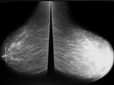

Tanı YöntemleriKafa içindeki lezyonların tanısı, genellikle hem klinik muayene hem de görüntüleme yöntemleri ile konulur. Kullanılan başlıca yöntemler şunlardır: